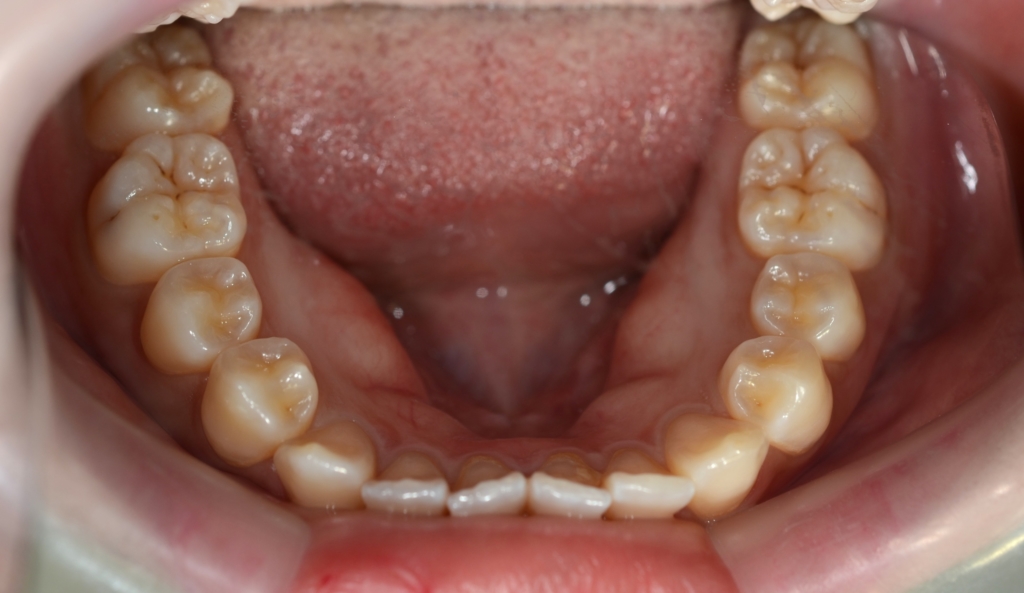

【診断】

#1.上下顎前突

(噛み合わせは上顎前突傾向)

#2.歯と顎の不調和による(軽度の)叢生

【治療方針】

1.上下左右の奥歯を1本ずつ抜歯してスペースを作り、前歯の軽度の乱れを改善

2.残りのスペース分を使い、上下前歯を最大限に後方へ移動

3.アンカースクリューを用いて上の歯列全体を更に後方へ移動させる

という治療計画にて、矯正を進めることにしました。